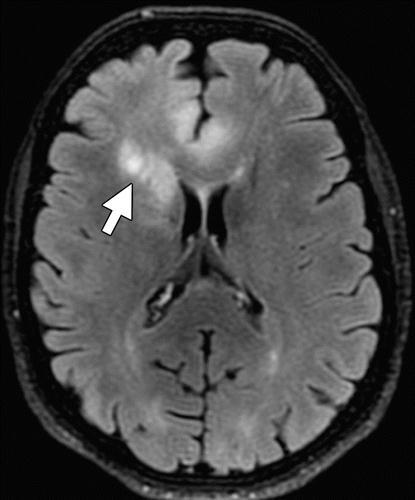

Fig.1. IllustrationsofCancerous&Non-CancerousCells (A) (B) (C)

(a)Normalimage.(b)Non-Cancerous(Benign).(c)Cancerous (Malignant).

Fig.2.IllustrationsofNormal,Benign,andMalignantimages.